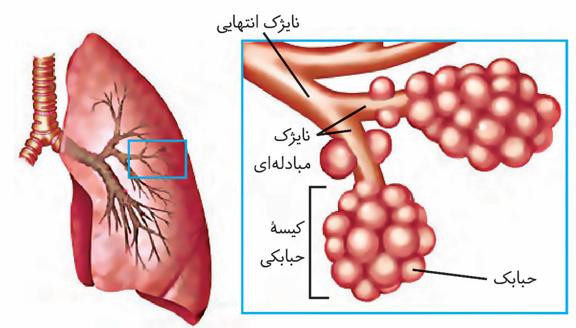

هر کلیه از حدود یک میلیون گُردیزه تشکیل شده است که فرایند تشکیل ادرار در آنها انجام میشود. ابتدای گُردیزه شبیه قیف است و کپسول بومن نام دارد.

بخش قیف شکل کلیه: لگنچه و بومن.

ادامه گُردیزه، لولهای شکل است و در قسمتهایی از طول خود، پیچخوردگیهایی دارد و براین اساس، به قسمتهای مختلفی نامگذاری میشود. این قسمتها به ترتیب عبارتاند از لوله پیچ خورده نزدیک، قوس هنله که U شکل است و لوله پیچ خورده دور که گُردیزه را به مجرای جمعکننده متصل میکند.

هر گردیزه ۴ بخش دارد: کپسول بومن، لوله پیچخورده نزدیک، قوس هنله و لوله پیچخورده دور.